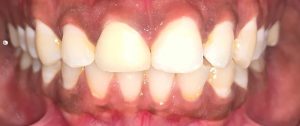

Department deals with all the treatments of teeth which alleviate pain due to pulp diseases and provide immediate solace to the patient. It also deals with the esthetic rehabilitation of the discolored, broken, mutilated teeth. Advanced endodontic treatment including micro-endodontics and regenerative therapy are also performed. Our department aims at creating and achieving excellence in the field of research and scientific development.

TREATMENTS

SERVICES